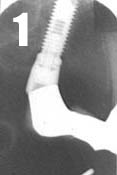

After preparing and laying open the supporting teeth, in this case nos. 13 and 11, the abutment is provided with an impression coping (Fig. 2). An impression is taken with an elastomer. The bridge is made of porcelain fused to metal with an intracoronal attachment, in this case McCollum, and with a palatinally placed horizontal locking screw which prevent vertical gliding (Fig. 3). The construction allows the implant-supported portion of the bridge to be taken off when necessary, e.g. when tightening the abutment screw. The bridge is cemented in the usual manner on the supporting teeth with simultaneous tightening of the gold screw in the implant-supported section. The bridge is cemented (Fig. 4), smile! (Fig. 5).